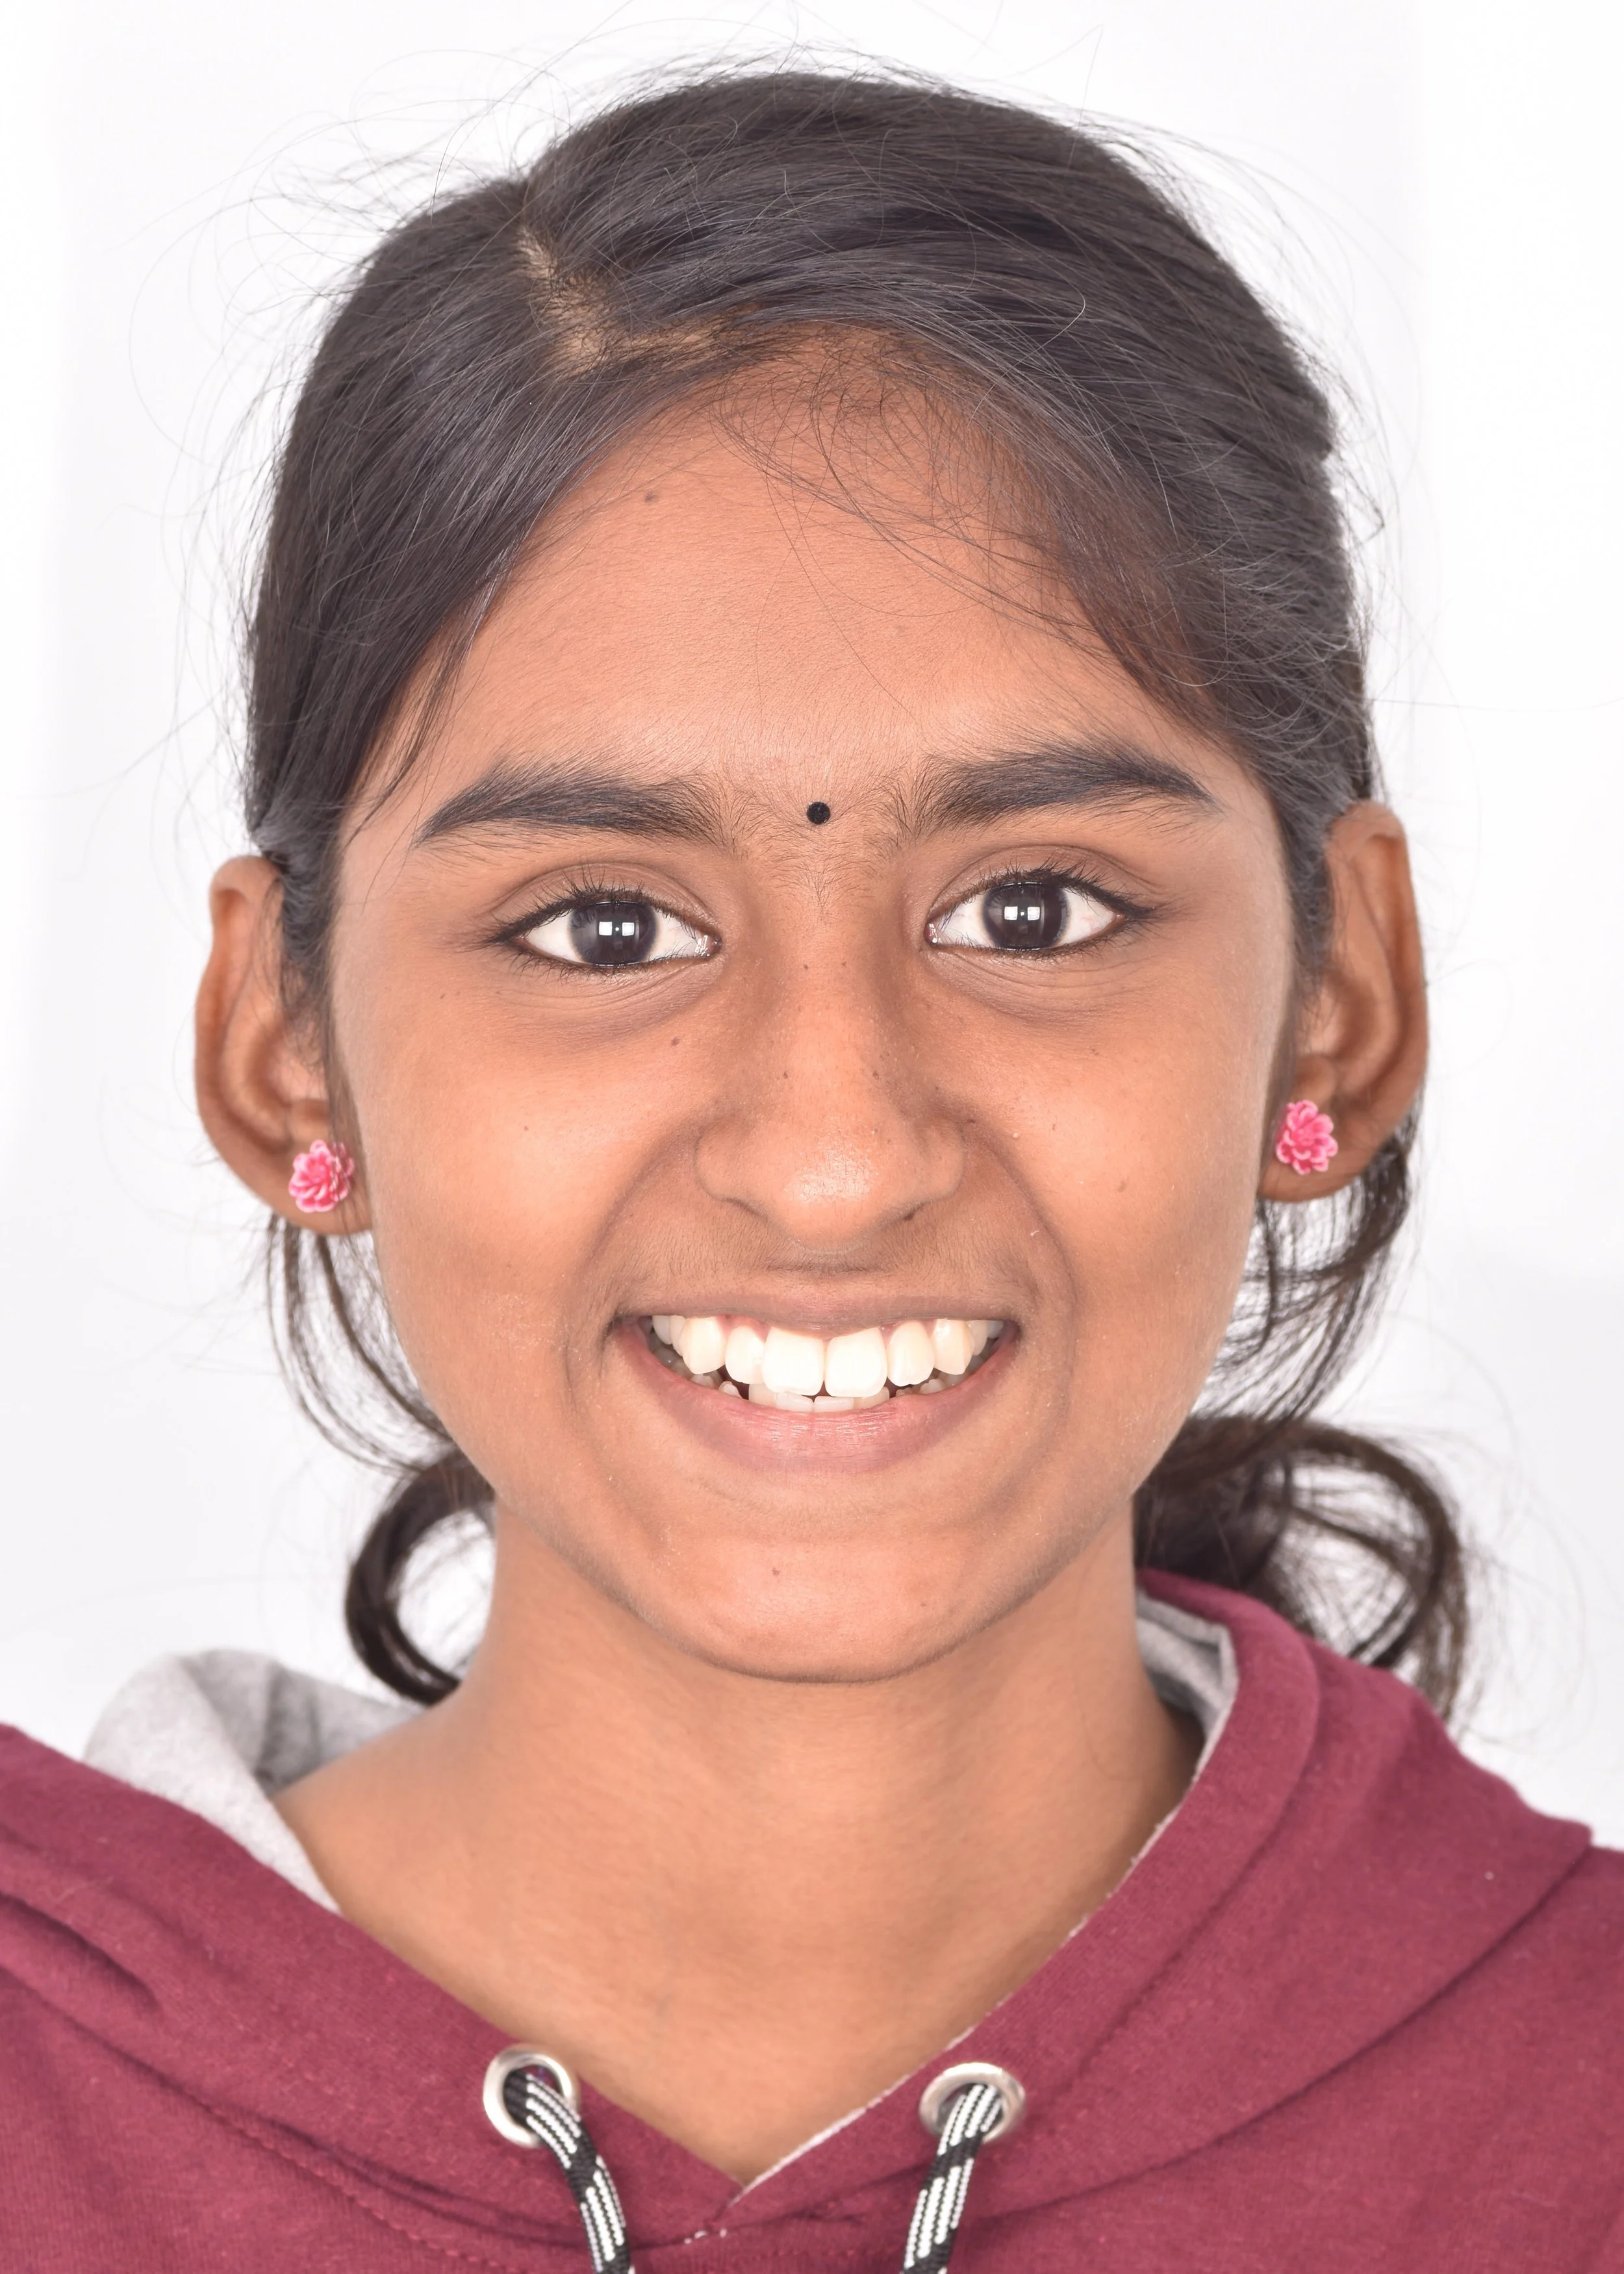

smile makeover

Smile Journey!

May be it is too simple to treat but the way this smile makeover made a difference in her life is immense! thats how wonderful smile curves are created!